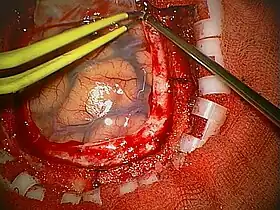

A craniotomy is a surgical operation in which a bone flap is temporarily removed from the skull to access the brain. Craniotomies are often critical operations, performed on patients who are suffering from brain lesions, such as tumors, blood clots, removal of foreign bodies such as bullets, or traumatic brain injury, and can also allow doctors to surgically implant devices, such as deep brain stimulators for the treatment of Parkinson's disease, epilepsy, and cerebellar tremor. The procedure is also used in epilepsy surgery to remove the parts of the brain that are causing epilepsy.

Human craniotomy is usually performed under general anesthesia but can be also done with the patient awake using a local anaesthetic; the procedure, typically, does not involve significant discomfort for the patient. In general, a craniotomy will be preceded by an MRI scan which provides an image of the human brain (brain in general) that the surgeon uses to plan the precise location for bone removal and the appropriate angle of access to the relevant brain areas. The amount of skull that needs to be removed depends on the type of surgery being performed. The bone flap is mostly removed with the help of a cranial drill and a craniotome, then replaced using titanium plates and screws or another form of fixation (wire, suture, etc.) after completion of the surgical procedure. In the event the host bone does not accept its replacement, an artificial piece of skull, often made of PEEK, is substituted. (The PEEK appliance is routinely modeled by a CNC machine capable of accepting a high resolution MRI computer file in order to provide a very close fit, in an effort to minimize fitment issues, and therefore minimizing the duration of the cranial surgery.)